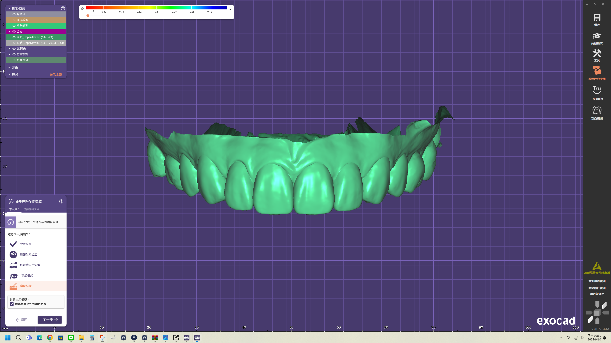

全瓷貼片是以高級陶瓷原料製成的薄透牙貼,和全瓷冠具有相同的優點;製程數位化,從口腔掃描、3D建模到齒型排列都有精確的模擬與設計,並參考大量數據以做出最符合病患需求的貼片。

更重要的是,如此精密的療程可於一日內完成!除了數位化大幅減少試戴與修改的時間,診所內也配置專屬牙技師團隊,吳冠儒牙醫師同步參與診療、即時溝通反饋,並精確作出成品,讓您美齒的夢想一日圓滿!